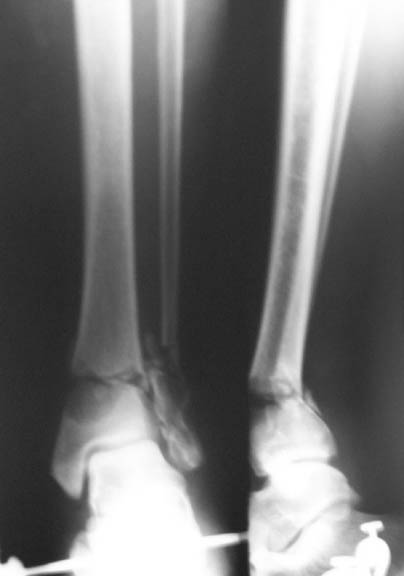

Thank you all for the kind responses. Kindly find attached the post op picture. I did an Ilizarov ring fixation which extended to the calcaneum. There was multiple small areas of partial thickness skin necrosis anteriorly and laterally which required split thickness skin graft.

Ilizarov device is a good choice, but I'm concerned about the valgus angulation (> 15degrees ?).

i would therefore, as a general rule, try my utmost to put in more wires in the distal fragment to gain a good hold + compression across the fracture site adds a lot to the stability of the frame. usually, in stable configuration of fractures, like your patient has, the calcaneal fixation then becomes redundant. you would need to compress this fracture further, judging from the xrays

1. The reduction is in Valgus. Which you could correct on the Ilizarov and

2. The Lateral Malleolus is about 6mm superior to its normal position, which I don't know how you could correct.

Why connecting rods are bent?

As Dr Finlayson commented the fragments are malaligned. The combination of wires and pins in the middle ring makes correction at least inconvenient though of course it is always possible to re-assembly the frame and include hinges.

It would be quite enough to have either a 6 mm half pin or a olive wire inserted in frontal plane just above the fracture. The pin or wire would help to move the distal part of the shaft laterally (and a bit back) to align the fracture.

To give the follow up on this patient: A repeat X-ray showed the talus subluxating laterally. A dynamic inversion and eversion strain view pictures showed the lower tibio-fibular syndesmosis opening out. The frame was re-adjusted. Fracture site compressed and valgus corrected. A syndesmotic compression was achieved by adding a washer to the olive and pulling the comminuted lateral malleolus medially. another olive with washer given through talus lateromedially. The equinus that you may see has been corrected. Pictures attached. would welcome critical comments.